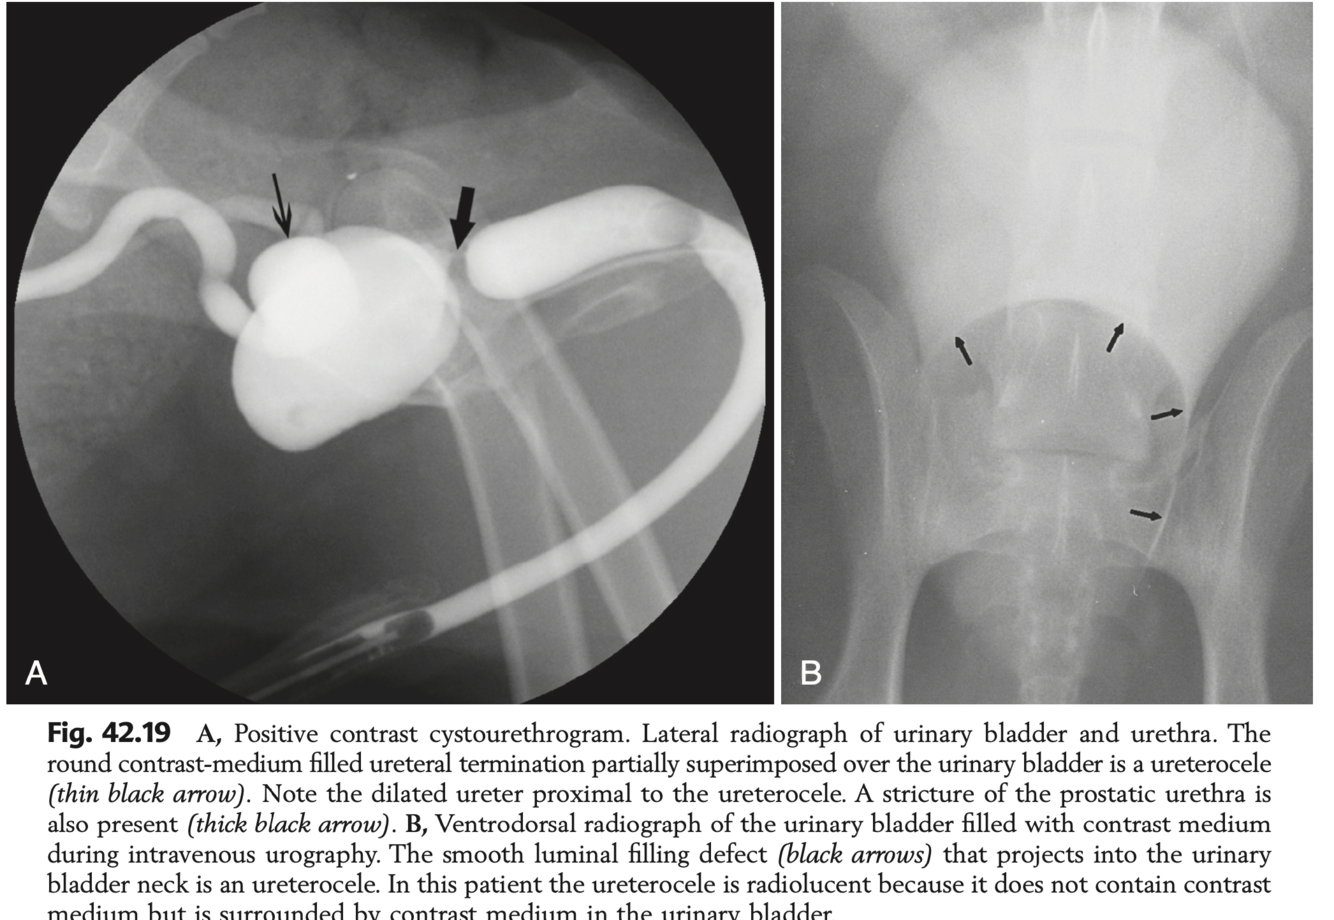

What creates the “cobra-head” sign?

Ureterocoele which communicates with bladder lumen, and takes up contrast